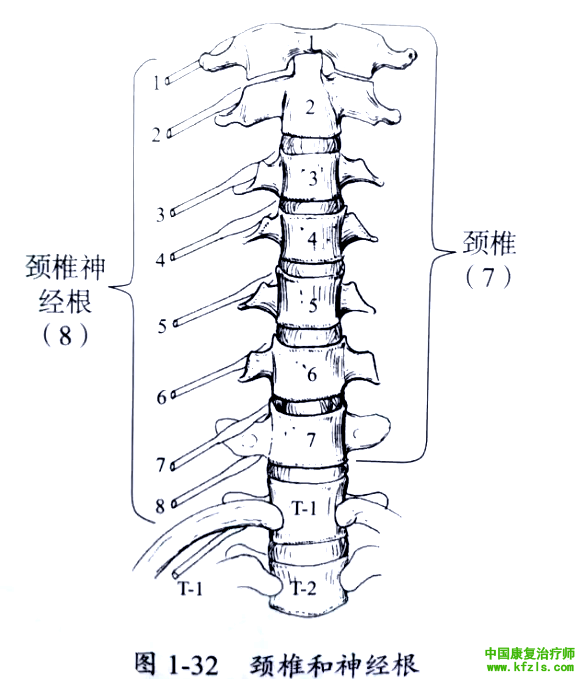

颈椎包括7个椎体,8对神经根。其中第1神经根位于枕骨和C1椎体之间,第6 神经根位于C5和C6椎体之间,第8神经根位于C7和T1椎体之间(图1-32)。